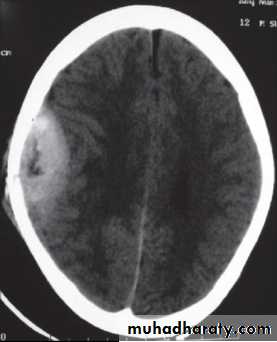

• Computed Tomography scan (CT scan) with/without contrast• Magnetic Resonance Imaging (MRI) with/without contrast